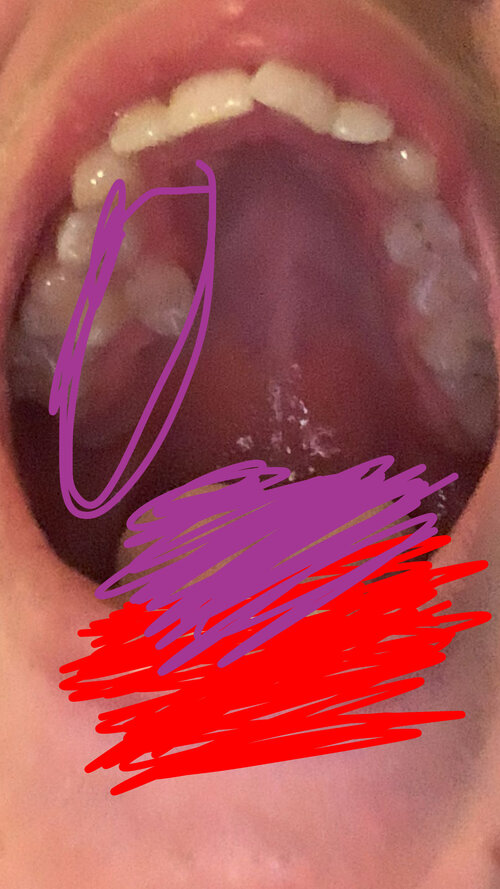

I have a narrow palate and I want to get a palate expander looking for any infortmation Js for tips to get the best results, anything in general THATS useful. (Only one side has badly misaligned teeth the other side is fine) also put a picture of my face showing the noticeable deformity on side of teeth that are misaligned.